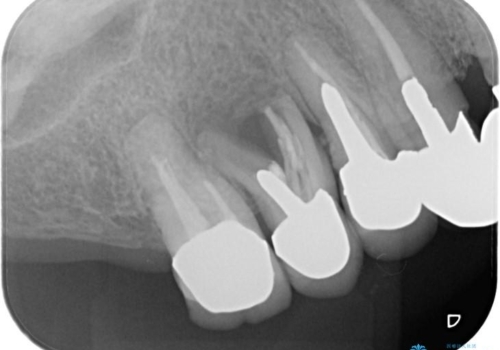

上顎は歯根破折と排膿が認められ、下顎も骨吸収により残せる状態ではないと判断し、抜歯後にインプラント治療(右上567、右下67)を行うことになりました。

骨吸収により上顎の骨量が少なかったため、インプラント埋入時にソケットリフトで骨補填材を填入も行いました。